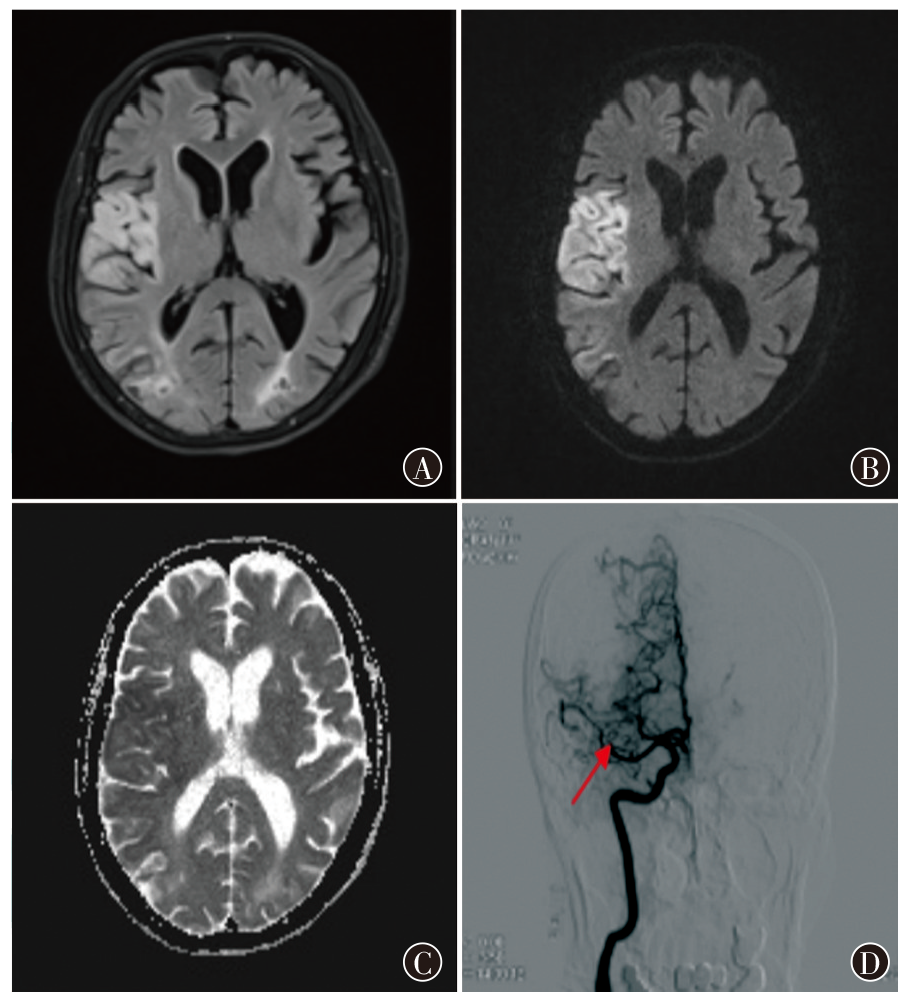

Kim JM, Jung KH, Park KH, et al. Clinical manifestation of cancer related stroke: retrospective case-control study[J]. J Neurooncol, 2013, 111(3): 295-301. DOI: 10.1007/s11060-012-1011-4.

Schwarzbach CJ, Fatar M, Eisele P, et al. DWI lesion patterns in cancer-related stroke—specifying the phenotype[J]. Cerebrovasc Dis Extra, 2015, 5(3): 139-145. DOI: 10.1159/000439549.